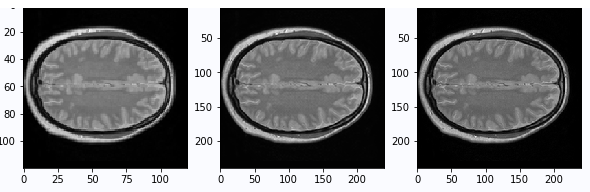

In [8]

# 查看MRI图像

import matplotlib.pyplot as plt

aa = train_LR_data[0,:,:]

bb = train_HR_data[0,:,:]

# 归一化

aa = (aa-aa.min())/(aa.max()-aa.min())

bb = (bb-bb.min())/(bb.max()-bb.min())

fig = plt.figure(figsize=(10,10))

plt.subplot(2,3,1)

plt.imshow(aa,cmap='gray')

plt.subplot(2,3,2)

plt.imshow(bb,cmap='gray')

print(aa.min(),aa.max())

print(aa.min(),bb.max())

plt.show()0.0 1.0 0.0 1.0

<Figure size 720x720 with 2 Axes>